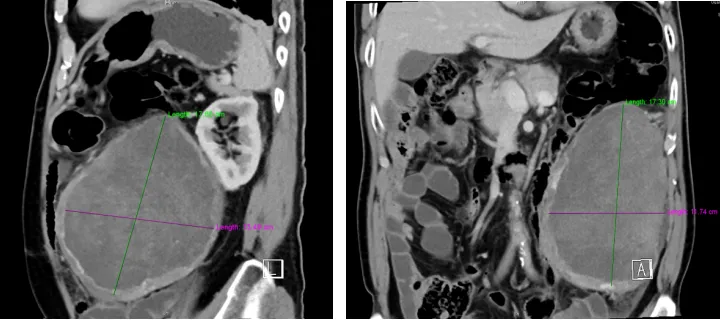

据了解,患者今年70岁有余,3年前因左肾上腺脂肪肉瘤接受过开放手术治疗。两个月前,患者因身体不适复查时,被确诊为肿瘤复发,且肿瘤体积已生长至18×18×14cm。为得到进一步治疗,患者慕名来到我院泌尿外科就诊。

王伟医生团队在了解患者情况后,为其进行全面检查。经CT检查显示,复发的肿瘤与腹主动脉、胰腺及肠道形成了广泛致密粘连,手术分离难度大,且术中可能有大出血、脏器损伤等风险。